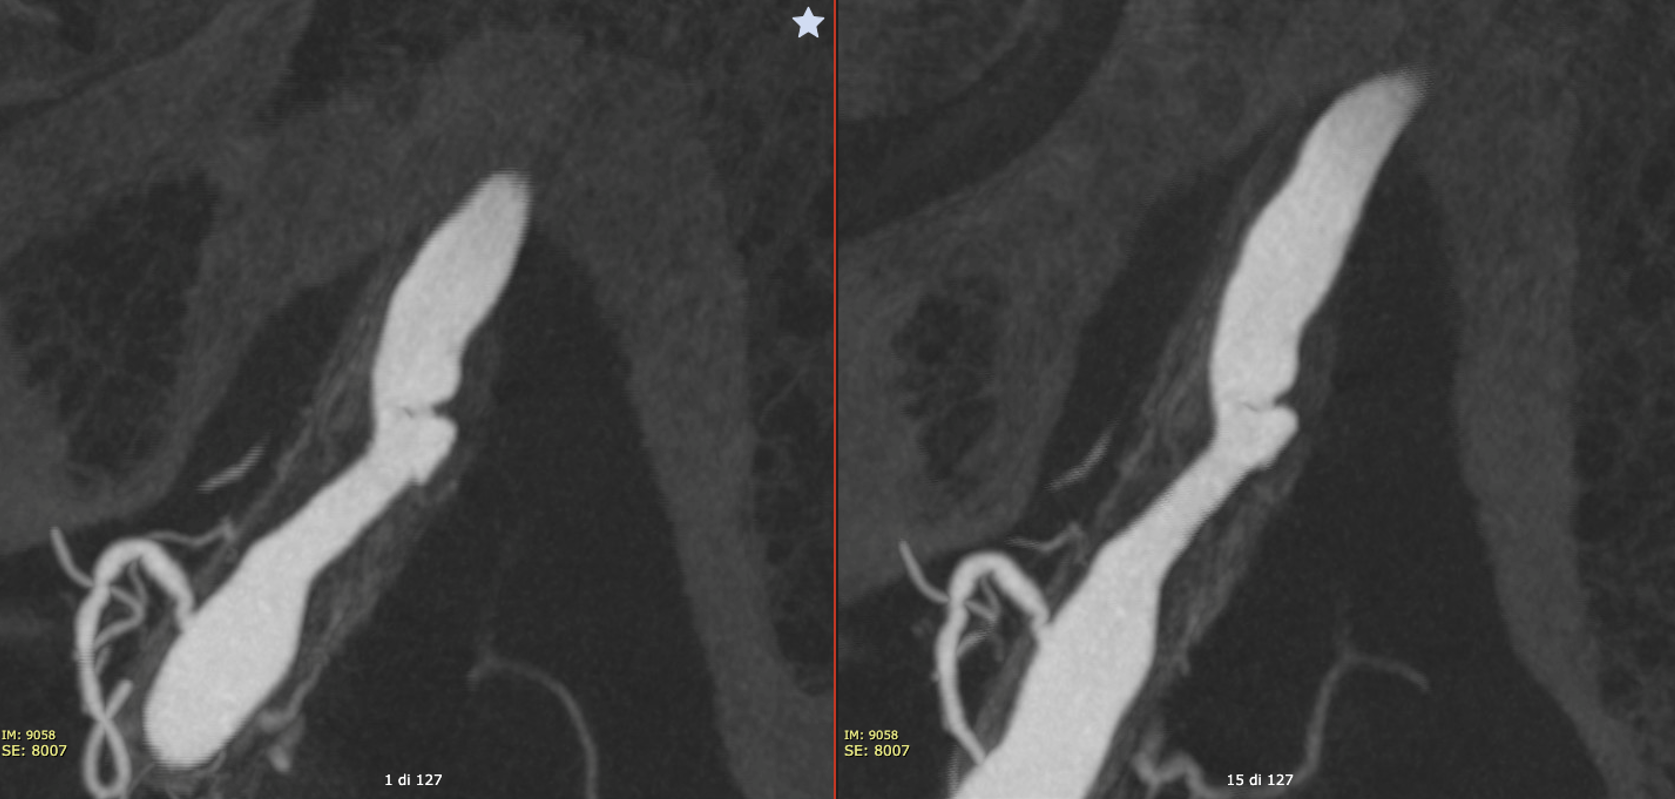

Vaso-CT images are much more detailed. (Vaso-CT protocol 22 cm FOV, 20 seconds acquisition, 20 ml pure contrast (300 mg/ml) manual injection, reconstructed with 50% FOV and 5123 matrix).

Here we can clearly see the vessel wall. The irregular shape of the plaque with ulceration is clearly visible. How much worse does the plaque look?

More! The thickened wall and relationship with several small branches suggests mix of calcification and vasa vasorum

Here we can see how the pial connections with the lateral spinal artery (arrow) recanalize the branch that lost its origin from the vertebral artery because of the plaque (dashed arrow)

Stenting

After stenting (Vaso-CT protocol 22 cm FOV, 20 seconds acquisition, 20 ml 50% contrast (300 mg/ml) manual injection, reconstructed with 50% FOV and 5123 matrix), we can still see the ulceration of the plaque, that is filled by the contrast, and the the distal end of the stent not completely apposed to the vessel wall. In these cases, we prefer avoiding overinflation of the balloon because of the risk of rupture of the artery.